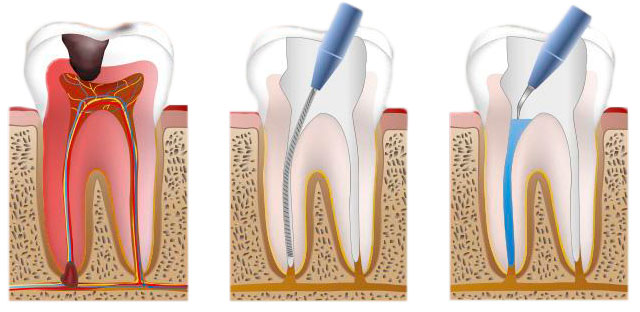

La endodoncia es el tratamiento que comúnmente conocemos como tratamiento de conductos, se hace con el fin de eliminar procesos infecciosos o dolorosos como abscesos dentales, fracturas, caries y /o restauraciones dentales extensas.